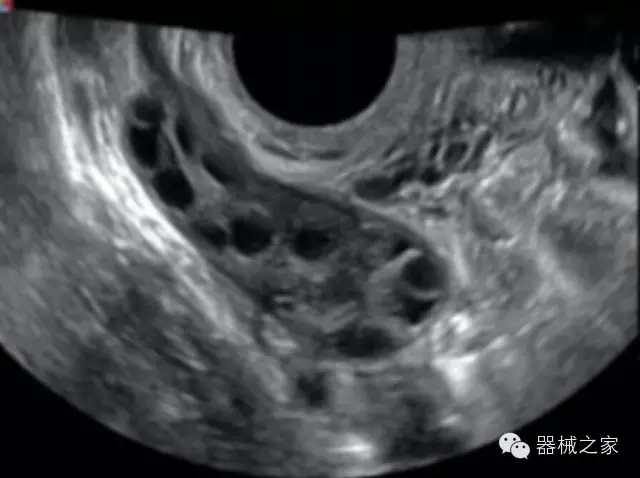

品牌:開立(SONOSCAPE)

公司簡介:

官方網(wǎng)站:www.sonoscape.com.cn

經(jīng)典產(chǎn)品:S8EXP

臨床圖片賞析

產(chǎn)品特點

·高效3D/4D成像技術(shù):高速的4D幀頻,豐富的3D成像模式,智能斷層切片功能;

·獨有的大角度及實時溫控技術(shù),能同一切面顯示宮頸及宮體,有效減低了患者的痛苦,及保護粘膜保證了醫(yī)療安全;